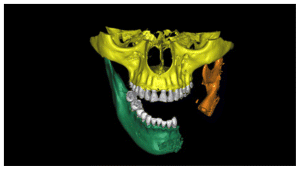

In the CT scan, the bone regeneration of the morphogenetic protein BMP2 (Cowell PLUS BMP) and the growth factors with the Chucron technique were verified, managing to observe a good bone conformation, however, a bone formation was observed towards the upper part of the jaw that did not follow any anatomical pattern of the mandibular body and was attached to the mandibular body. (Figures 19,20, 21)